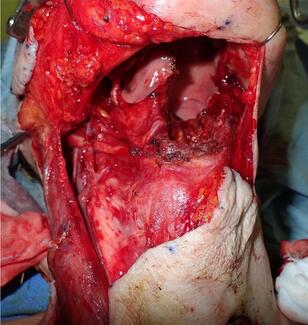

Masakatsu Hihara, MD, PhD; Natsuko Kakudo, MD, PhD; Michika Fukui, MD; Toshihito Mitsui, MD; Maako Fujita, MD; Ai Satou, MD; Maki Okamoto, MD; Ayako Kako, MD

The supercharged pectoralis major musculocutaneous flap was introduced in a patient who was at high risk for partial necrosis of the flap and underwent surgery for reconstruction of the tongue.